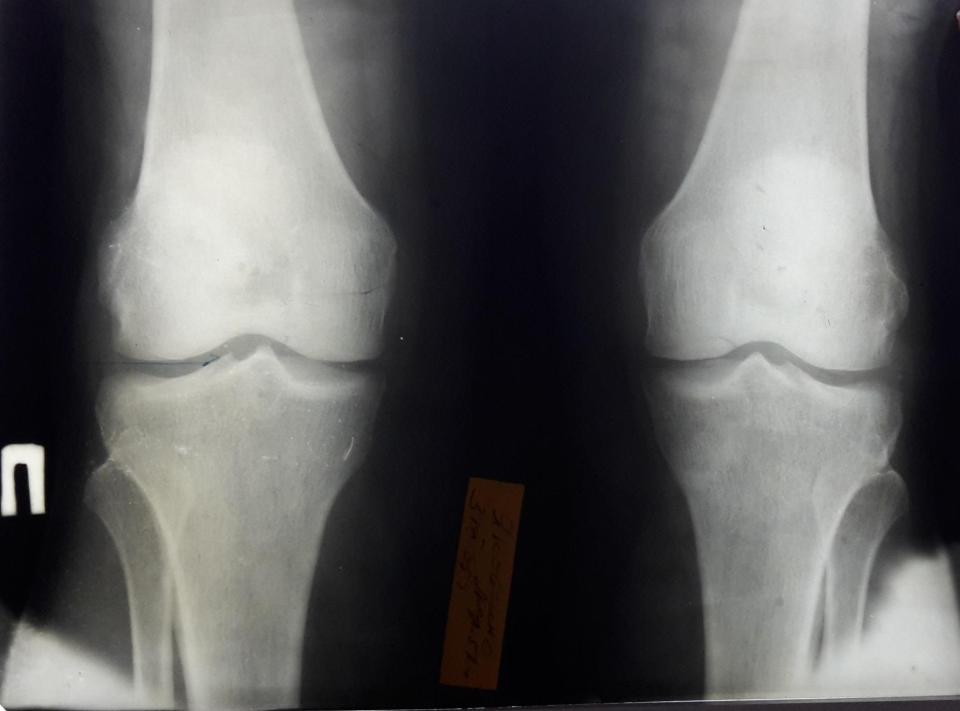

Пример деформирующего артроза коленного сустава.

Резкое сужение внутренней части суставной щели свидетельствует о полном разрушении там суставного хряща. Видны субхондральный склероз и кистозная дегенерация под суставными поверхностями.